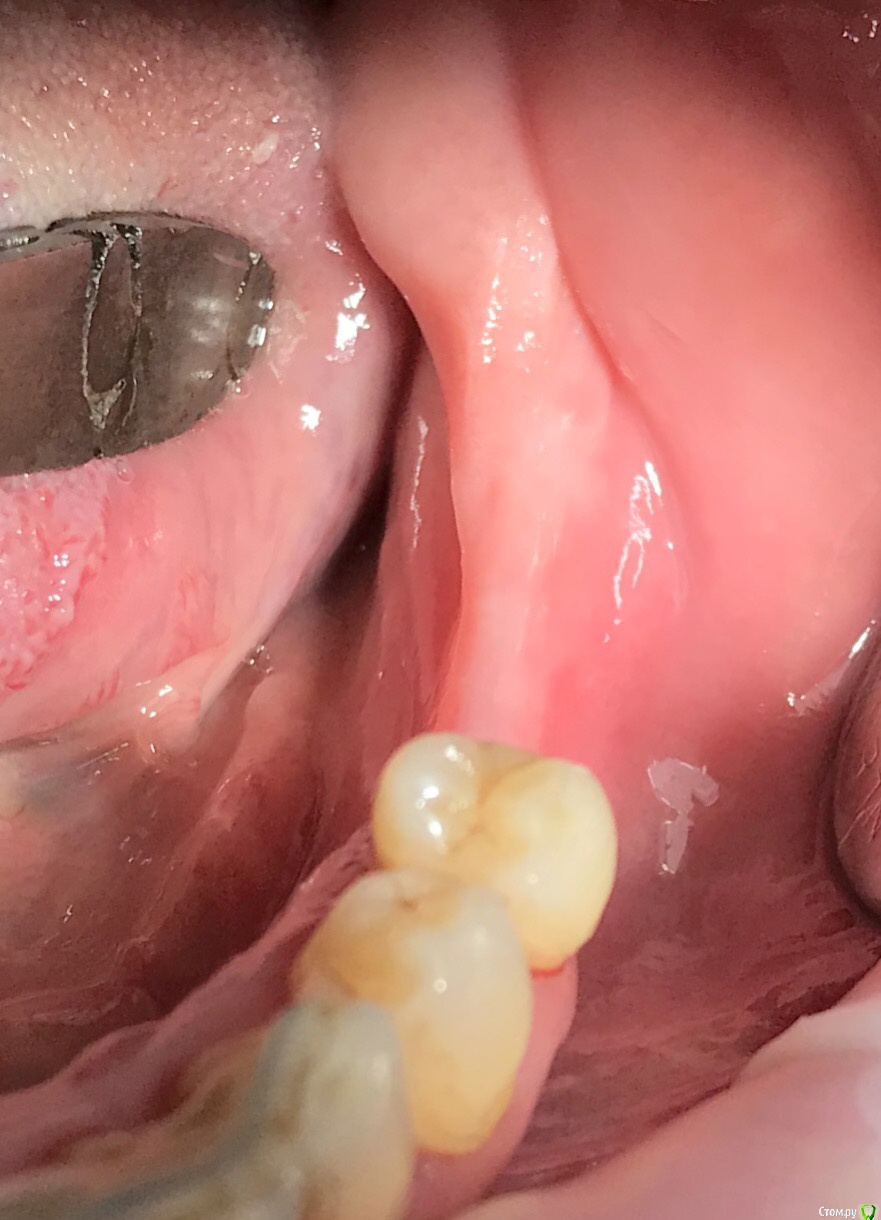

колесников Опубликовано 16 декабря, 2018 Автор Поделиться Опубликовано 16 декабря, 2018 (изменено) Поставлена задача:возместить дефект зубного ряда. Бюджет ограничен. Как видно по кт,для имплантации нет сложностей. Импланты Астра 4.0,поставлены с заглублением в оптимальной позиции. Дефицит прикреплённой слизистой вестибулярно у шеек имплантов возмещён роллом с гребня. Можно было этим ограничится. Однако при протезировании дефицит объема тканей будет очевиден. Роллы фиксированы к подвижной и тонкой слизистой,результат сомнительный,тк нет стабильности. Щечный тяж и скат гребня неминуемо приведут к рецесси слизистой у шеек имплантов. Можно было восстановить объём гребня при помощи нкр,затем лоскут с неба ( 1 год лечения). Или хотябы подсадить сст пожирнее.а потом асл (6мес),на первое время хватило бы. Но . Бюджет ограничен. Сроки тоже. Слово «костная пластика» вызывает панику. Новая задача: минимизировать вмешательства,убрать тяжи,создать объём,небо не трогаем. Проводим тоннельный графтинг. Получаем объём,поднимаем ткани и тяжи не тянут. Роллы получают покой ,стабильность и созревают в кратчайшие сроки. Графт поднадкостнично. Графт стабилен. Графт пропитался кровью,графт созревает. Результат быстрый. Дискомфорта 0. Затраты минимальные. Срок жизни такой пластики ни чем отличается от любой другой,в конечном итоге тает все. Если не стимулировать. Изменено 16 декабря, 2018 пользователем колесников 1 Ссылка на комментарий

колесников Опубликовано 17 декабря, 2018 Автор Поделиться Опубликовано 17 декабря, 2018 (изменено) Считаю как раз наоборот,к фдм можно подшиться ,зафиксировать,стабилизировать лоскут. Хуже когда сшиваешь 2 подвижных лоскута,все это гуляет над зоной вмешательства,а раз нет стабильности есть угроза расхождениям,инфицирования или фиброза.Хотя риск конечно есть,когда тонкая подвижная слизистая. Сначала я тоже боялся инфицирования в таких случаях,раскрывал расщепленно ,старался оставить прикрепление у шейки и ещё всякое разное,но потом понимание пришло,при поднятии тканей уходит напряжение и можно подшиться к фдм,разрывов,раскрытия,расхождения краев не происходит. Изменено 17 декабря, 2018 пользователем колесников Ссылка на комментарий